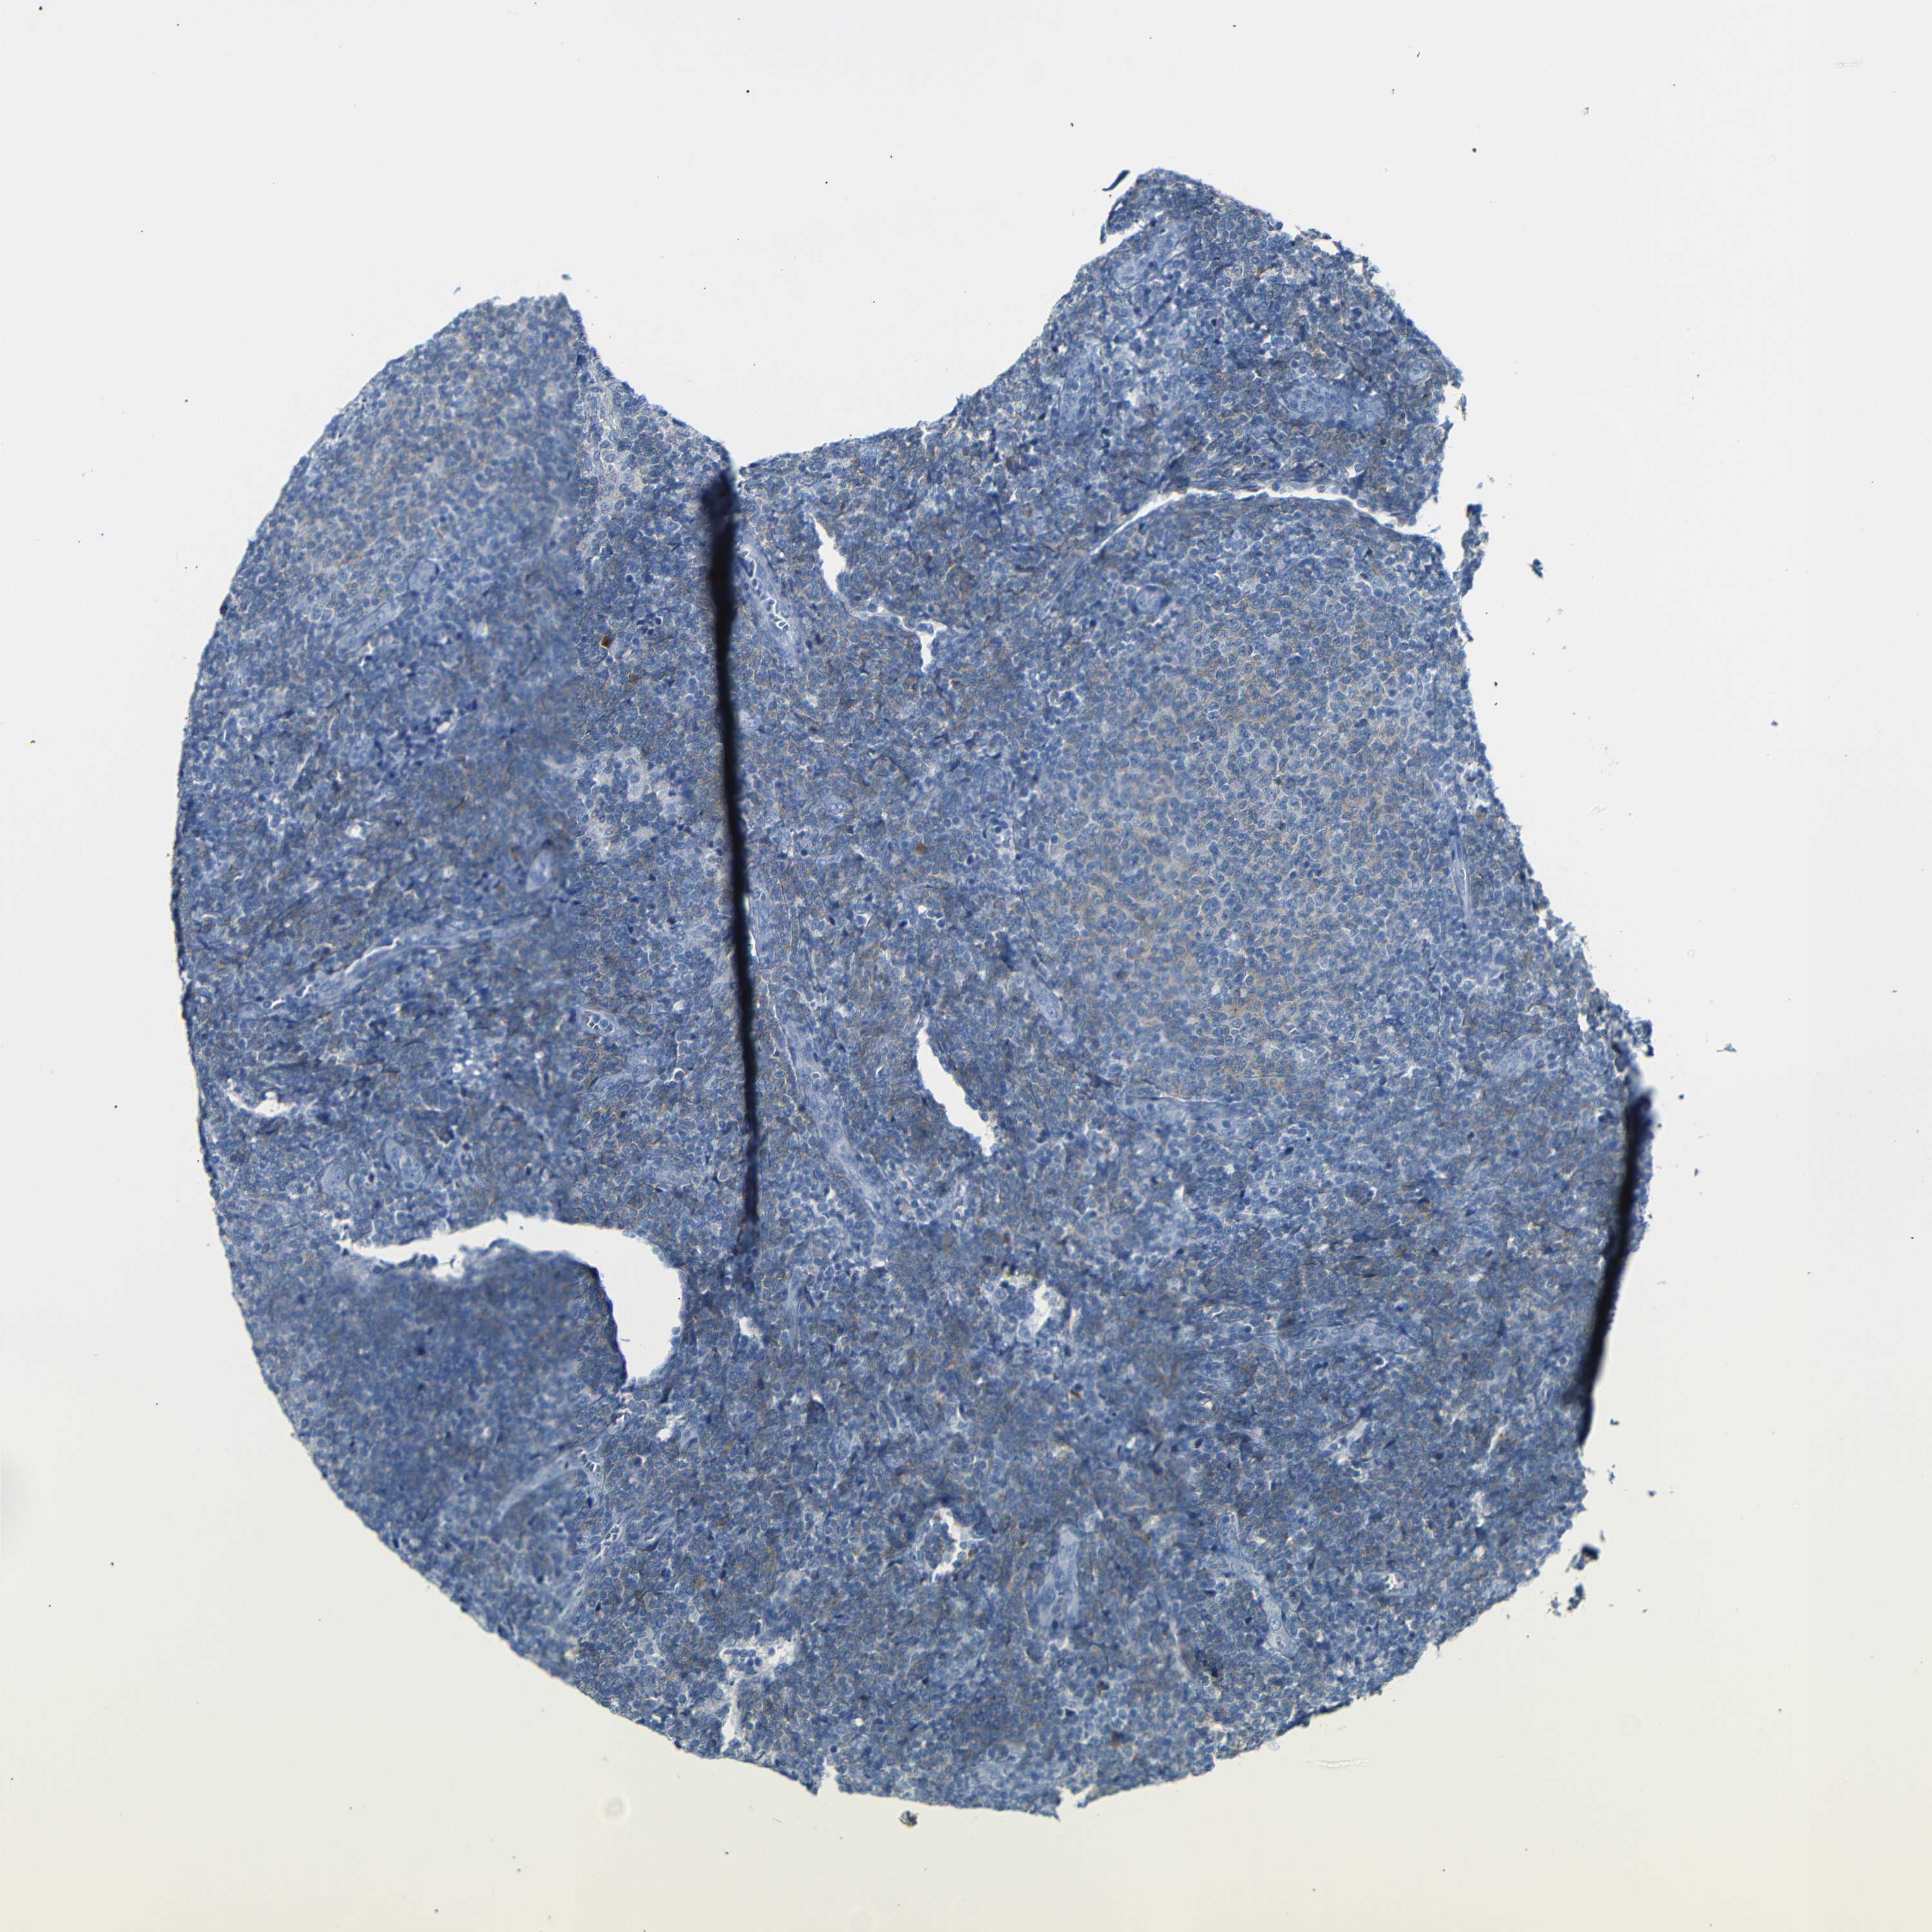

LYMPHOMA - Protein expressioni

A mouse-over function shows sample information and annotation data. Click on an image to view it in a full screen mode. Samples can be filtered based on level of antibody staining by selecting one or several of the following categories: high, medium, low and not detected. The assay and annotation is described here.

Antibody stainingi

Antibody staining in the annotated cell types in the current human tissue is reported as not detected, low, medium, or high, based on conventional immunohistochemistry profiling in selected tissues. This score is based on the combination of the staining intensity and fraction of stained cells.

Each image is clickable and will lead to virtual microscopy that enables deeper exploration of all samples and also displays staining intensity scores, fraction scores and subcellular localization as well as patient and tissue information for each sample.

Antibody HPA013323

Hodgkin's disease, NOS

Malignant lymphoma, non-Hodgkin's type, High grade

Malignant lymphoma, non-Hodgkin's type, Low grade